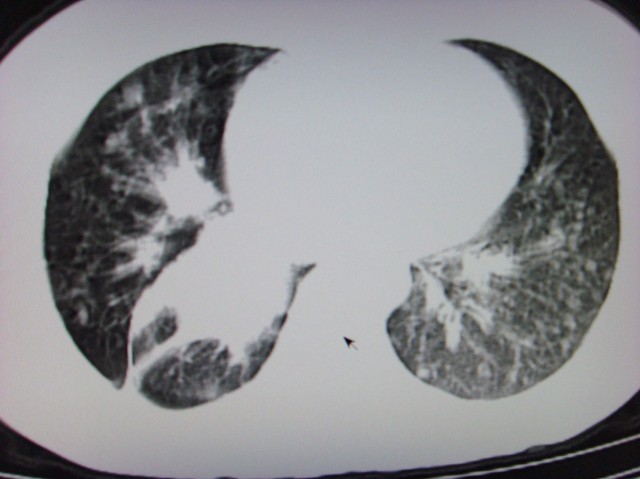

标题: CT7125:中央性肺Ca.

典型 中央型ca伴双肺、淋巴结转移

右下中心型肺癌伴双肺转移、纵隔淋巴结转移,癌性淋巴管炎可能性大

典型--右下中心型肺癌伴双肺转移、纵隔淋巴结转移,癌性淋巴管炎可能性大

中心型肺癌伴双肺转移及纵隔淋巴结转移,癌性淋巴管炎

典型的中央型ca,肿快和肺门分界不清,肿快边界模糊,呈毛刺状。伴淋巴结转移。